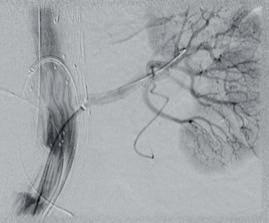

www.shapemem.com LIT1096 Rev A 0297 TrelliX® Embolic Coil IMPEDE® Embolization Plug IMPEDE-FX Embolization Plug IMPEDE-FX RapidFill® Device 5X © 2022 Shape Memory Medical Inc. All rights reserved. 807 Aldo Avenue, Suite 109, Santa Clara, CA 95054 USA +1.408.649.5175 | info@shapemem.com | www.shapemem.com Indications: The IMPEDE Embolization Plug, the IMPEDE-FX Embolization Plug, and IMPEDE-FX RapidFill are indicated to obstruct or reduce the rate of blood flow in the peripheral vasculature. The TrelliX Embolic Coil System is intended to obstruct or occlude blood flow in vascular abnormalities of the neurovascular and peripheral vessels. Indications include intracranial aneurysms, other neurovascular abnormalities such as arteriovenous malformations and arteriovenous fistulae, and arterial and venous embolizations in the peripheral vasculature. Refer to the IFU – supplied with each device – for a complete statement of the indications, contraindications, warnings, and instructions for use. Inferior Mesenteric (IMA) and Renal Accessory Artery angiographic image courtesy of Alexander Maβmann, MD, Saarland University Medical Center, Homburg/Saar, Germany. The images are illustrative and do not represent the actual size of any products. Patent: www.shapemem.com/patents Shape Memory Medical products and associated components are not available in all countries or regions. Please contact your Shape Memory Medical representative for details regarding product availability. Shape Memory Medical, IMPEDE, IMPEDE-FX RapidFill, and TrelliX are all registered trademarks of Shape Memory Medical. IMPEDE® Embolization Plug GENERATES NEW HEALING POSSIBILITIES CONFORMS TO THE ANATOMY UNPARALLELED VOLUME RETURNS CLARITY Supports thrombus formation throughout porous scaffold Reshaping your view of clinical success through the science of smart polymer Smart

Radiolucent smart polymer IMPEDE-FX Embolization Plug